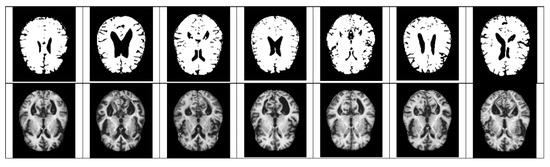

- For Z-score normalization, the interval to which each pixel belongs is converted to [−1, 1], and for min–max, it is converted to [0, 1]. During the computation of the convolutional neural network, the pixel intensity of [0, 255] is adjusted for fast convergence and accurate feature extraction.

- The size space of pixels constituting the Alzheimer’s MRI data set is [0, 255]. Among them, patients with AD with reduced hippocampus will have more pixels close to zero than normal people. On the premise of this, the average value of pixel intensities in each MRI image is set as a threshold value. Alzheimer’s should recognize changes in size contraction rather than changes in brain function. Based on this information, it is necessary to set the space as an important feature for the color information of MRI rather than a feature representing the shape of the brain.